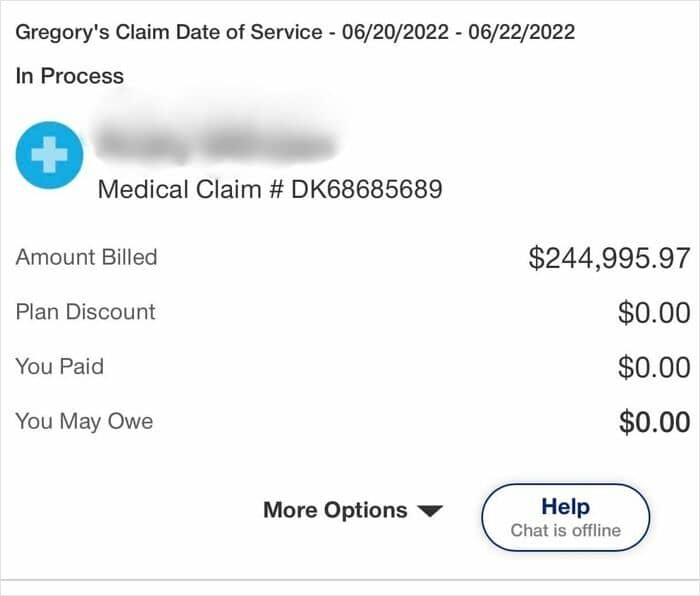

#45 My Kid Was In The Hospital For 3 Days Due To Pneumonia. Thank God We Have Insurance. I Don’t Know How Anyone Can Still Defend U.S. Healthcare